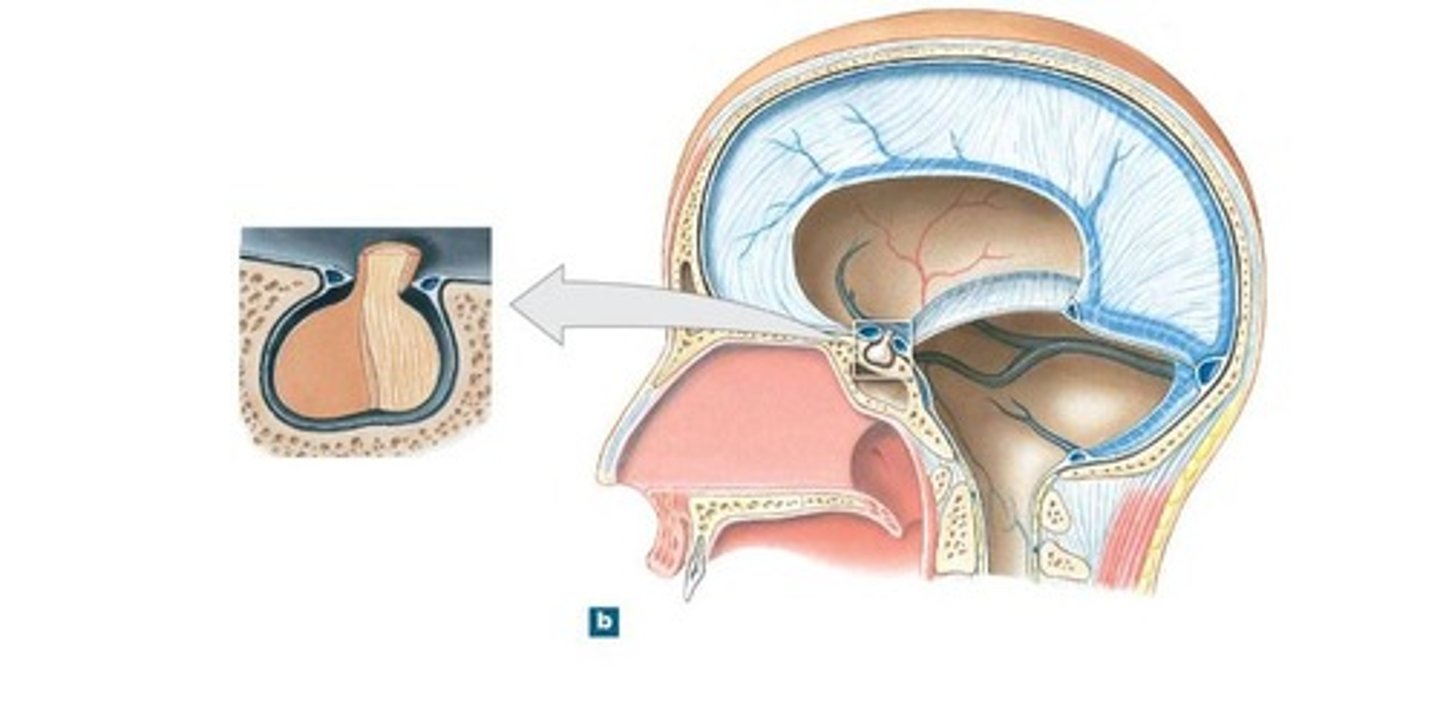

diaphragm sellae

smallest infolding covering pituitary gland & sella turcica